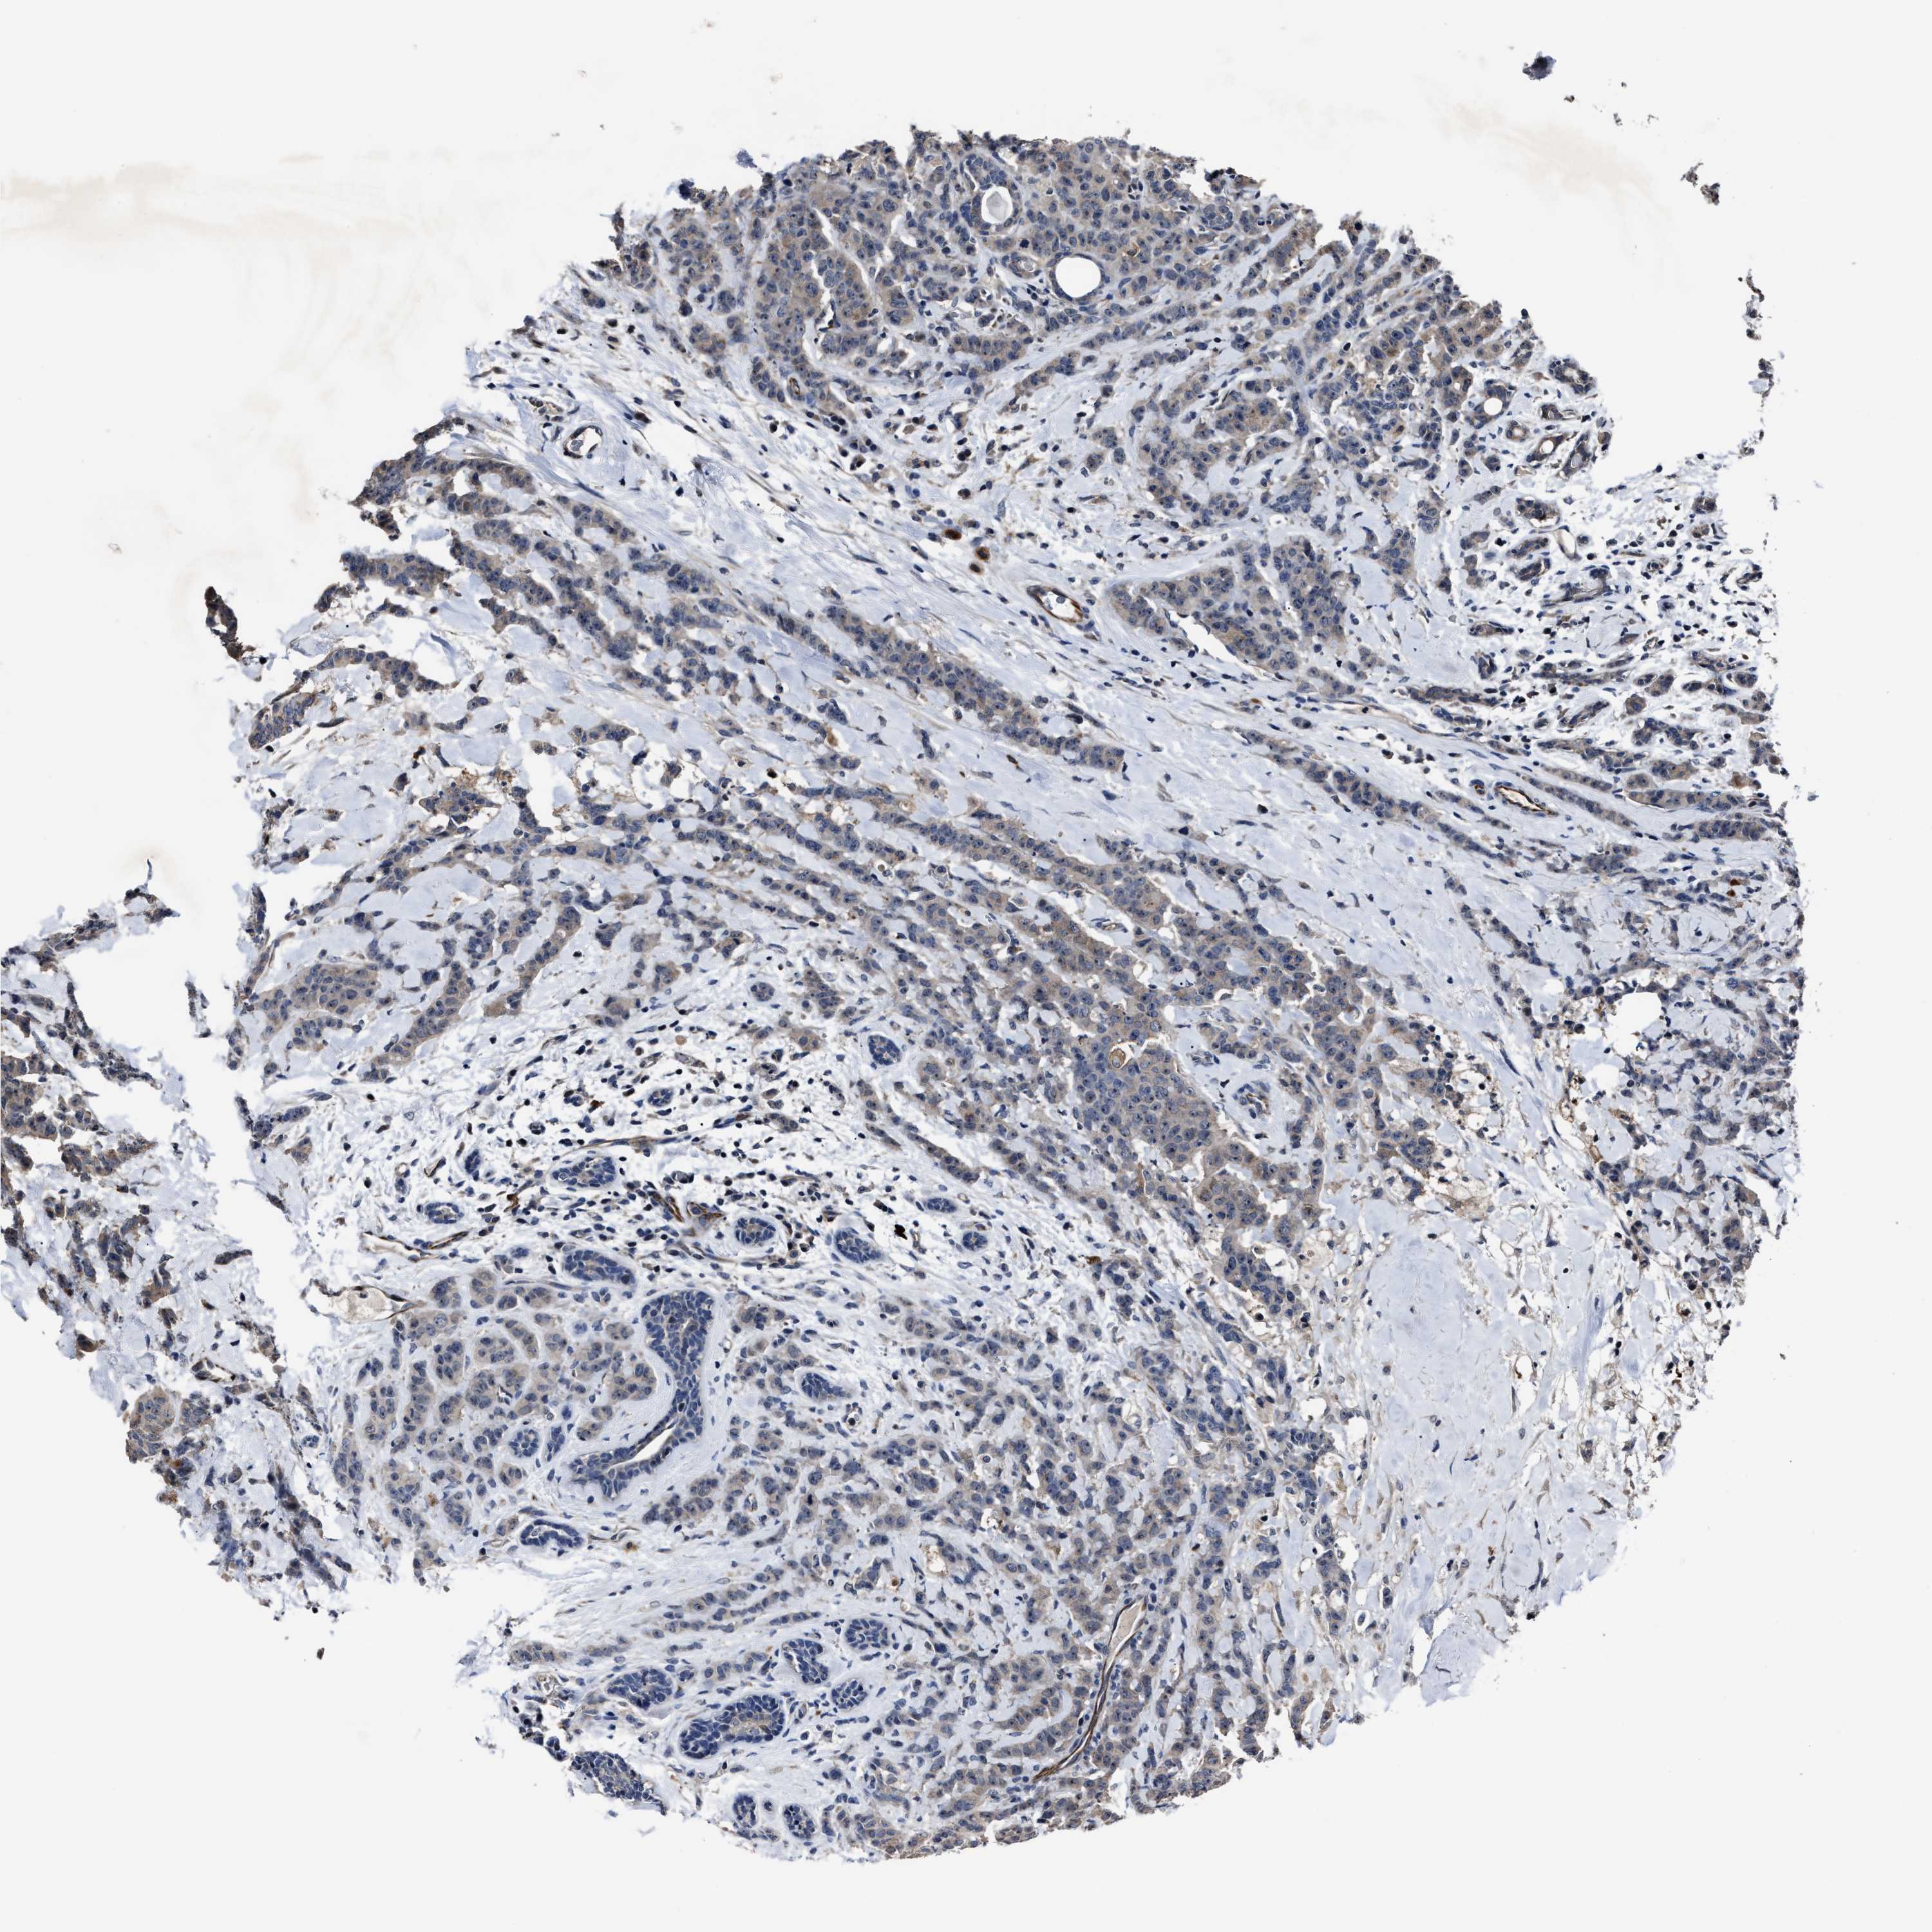

CANCER BREAST CANCER Show tissue menu

BRCA TCGA BRCA VALIDATION PROTEIN EXPRESSION